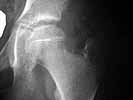

The eleven year old female gymnast presents with an xray image of the left hip which looks more benign than the MRI which shows coxa plana with resorption of bone in a large area of the femoral capital epiphysis and widening of the femoral neck. These changes and the patient's gender and age mean a poor prognosis for Legg-Perthes disease which I believe this case represents. Was the MRI done somewhat later in the course of time than the X-rays? I could not make out dates on the images. There is one feature of the MRI which might be favorable: the enlarging femoral head does not seem to extrude far beyond the edge of the acetabulum as marked by the thorn sign. This indicates that satisfactory containment might still be obtained by upper femoral varus-producing osteotomy. I would confirm this possiblity by a dynamic arthrogram at the time of surgery; if the femoral head centers well enough with up to 30 degrees abduction for the edge of the acetabulum to drop down around it, the upper femoral osteotomy might bring a good short term outcome. Otherwise, I might consider a double osteomy: upper femoral and innominate. Left alone, the hip will probably go on to hinge-abduction with attendant pain and stiffness.

But, her femoral head is still spherical, it looks to be about the same size as the other head, and her joint space is preserved. Those are all good things.